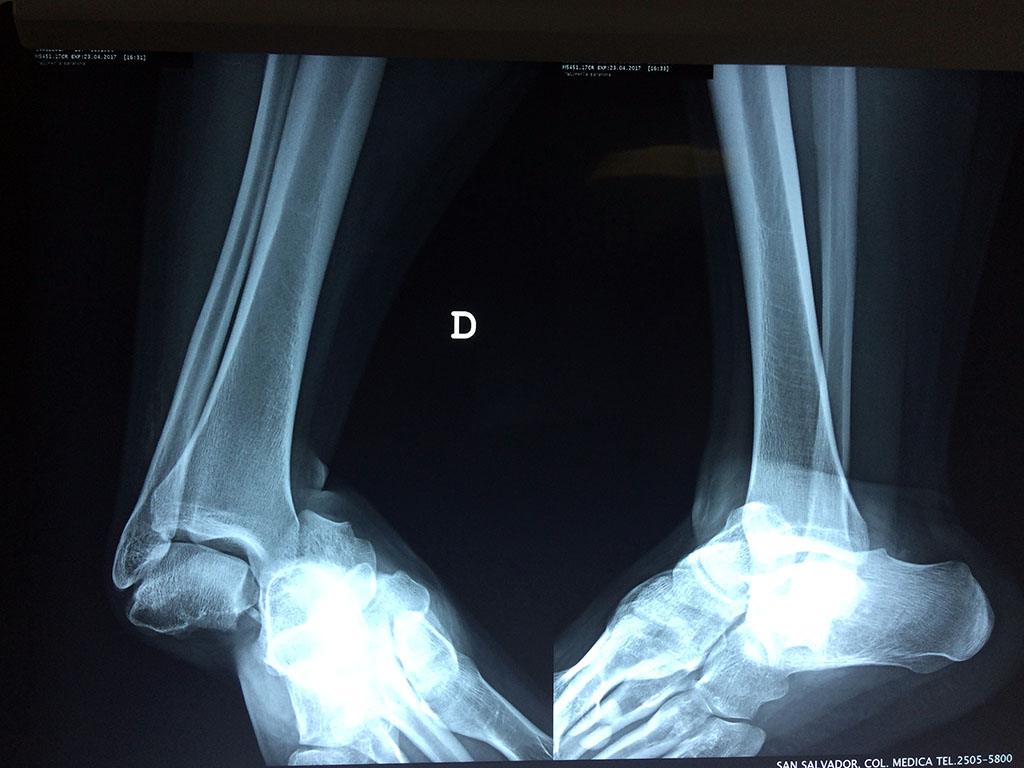

Algunas fracturas de tobillo pueden requerir cirugía si:

- Los extremos de los huesos están desalineados entre sí (desplazados).

- La fractura se extiende hasta la articulación del tobillo (fractura intra-articular).

- Los tendones o ligamentos (tejidos que sujetan los músculos y los huesos entre sí) están rotos.

- El médico cree que sus huesos probablemente no sanen apropiadamente sin cirugía.

- El médico considera que la cirugía puede permitirle una recuperación más rápida y confiable.

- En los niños, la fractura involucra la parte del hueso del tobillo donde el hueso está creciendo.